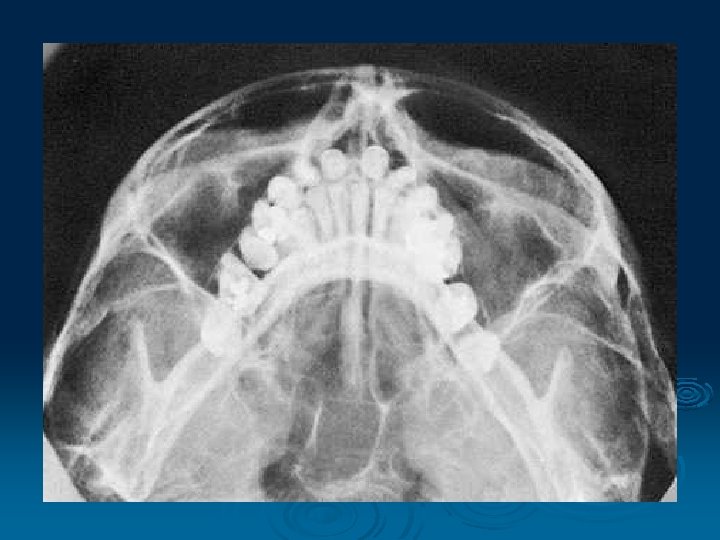

Submento-Vertical Projection

Hirtz' Projection § The vertical submental projection § The central ray is centred between the angles of the jaw the mandibular arch and condyles, the skull base, sphenoid sinus and the posterior ethmoid cells